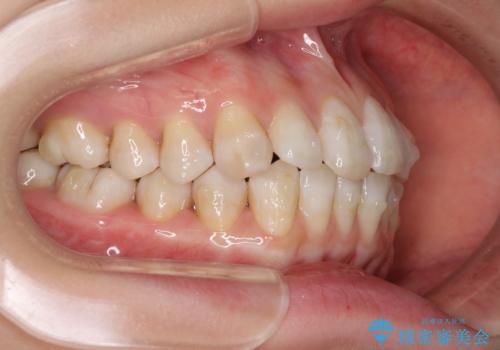

話しにくいオープンバイト インビザラインによる矯正治療

- 前歯の上下スペースによる話しにくさを気にして来院された患者様です。

インビザラインにより上下の前歯の隙間を閉じていくこととしました。

上下の奥歯を圧下させるようにすることで、前歯を接触させるように計画しました。

隙間に舌が入り込むことが話しにくさに繋がっていたため、舌の筋肉のトレーニングも並行して行い、話しにくさの改善と後戻りの抑制を図りました。